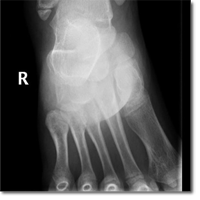

Niño de nueve años de edad sin antecedentes de interés que acude a Urgencias tras haberse caído...

Downey Carmona FJ.

09 diciembre 2014